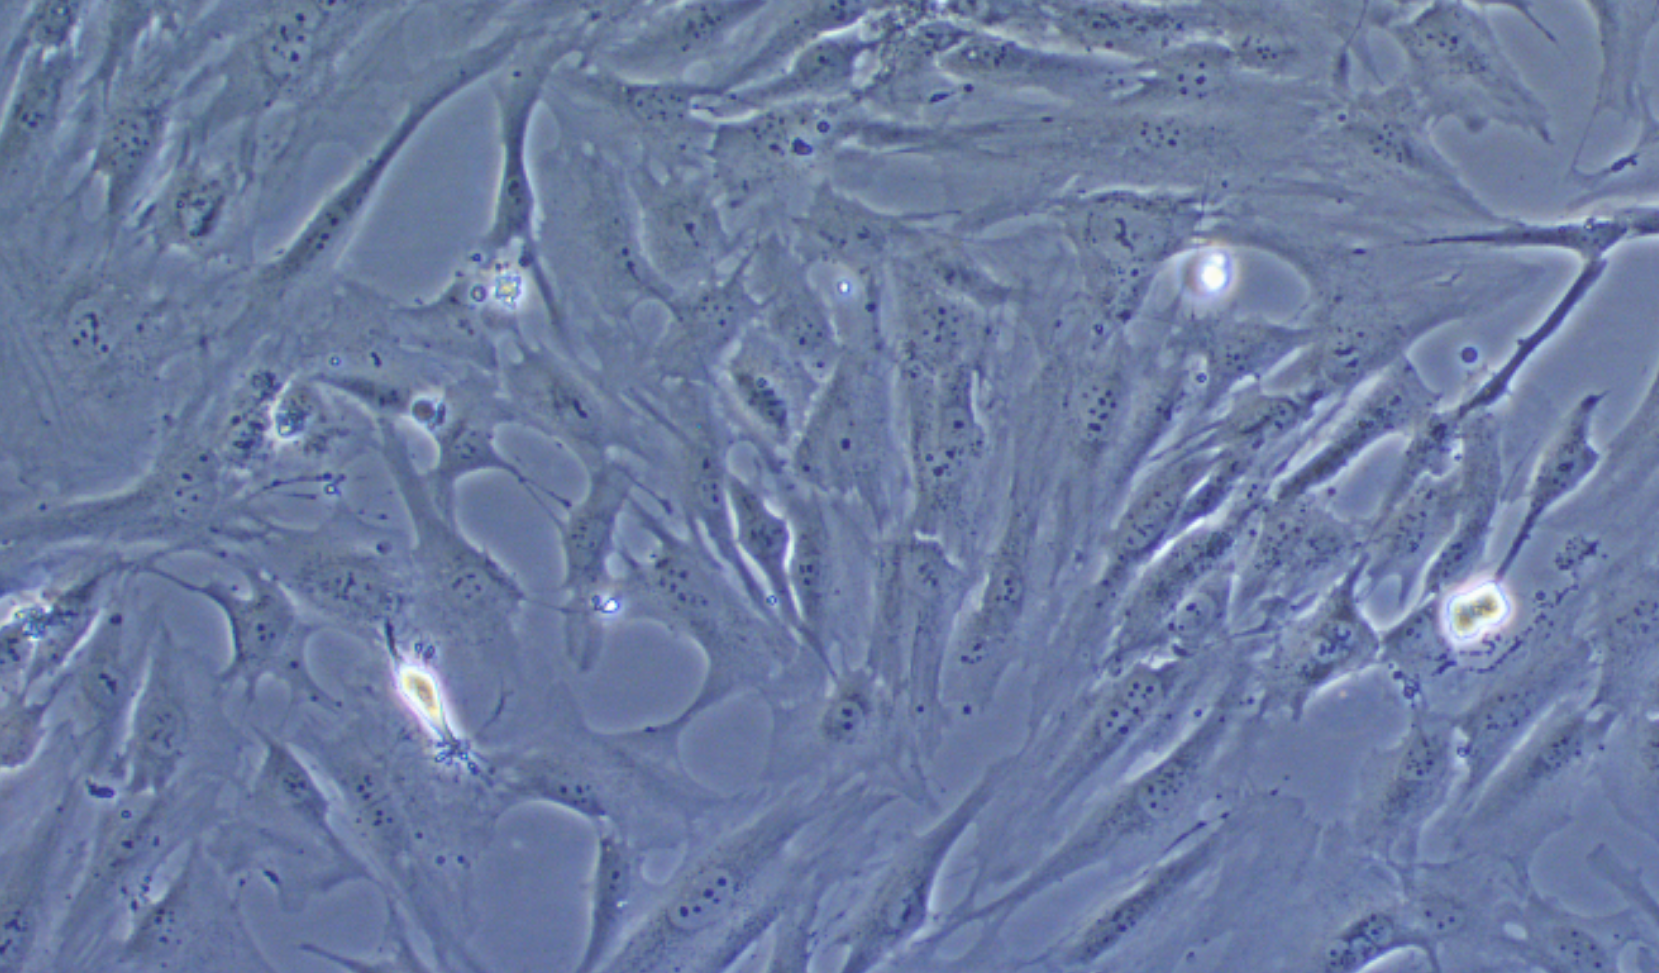

形態 |

長梭形細胞樣,不規則細胞樣 |

生長特征 |

貼壁生長 |